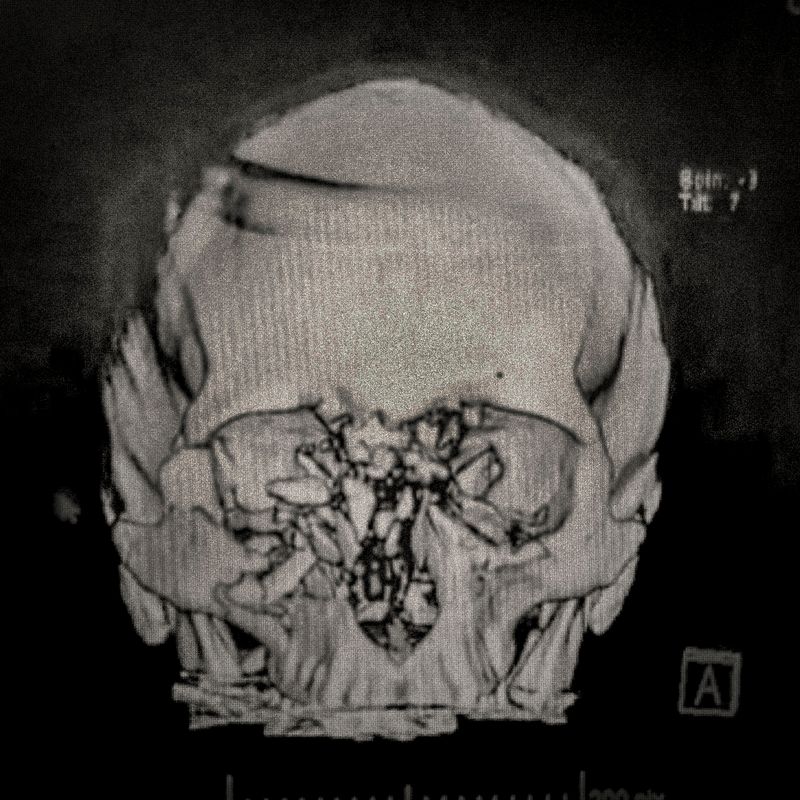

X-ray showing the pellet embedded in the skull of Ybar Soto (29) Ybar was hit by a pellet that lodged in his right eye on October 24, 2019 in Plaza Italia. Santiago. His diagnosis was ocular burst. Santiago, Chile. December 28, 2019

Ybar Soto (29) Electrical Technician Lives in Puente Alto,Santiago Ybar was hit by a pellet that lodged in his right eye on October 24th, 2019, at Plaza Italia, Santiago. His diagnosis was an eye burst. “If I would have shot the police in his eye, would they have me to signing once a month? I’ve had to face really hard situations, situations where I have seen the police looking at my face and laughing at me, because of the damage they did in my eye. What can I do against that? I can’t do anything. This is a huge anger and pain that is going to weigh me down my whole life. Until now I have the same answer. I do not regret for a fucking second going to protest that day because I am totally and absolutely convinced that we were not doing anything wrong. These are our rights.”